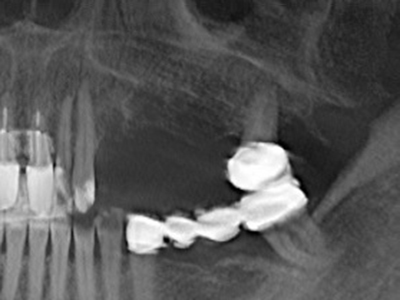

Fig. 15: The one-year follow-up x-ray examination shows stable conditions at the bone level.

Fig. 16: The intraoral conditions are also stable with embedding of the implants in keratinized gingiva.